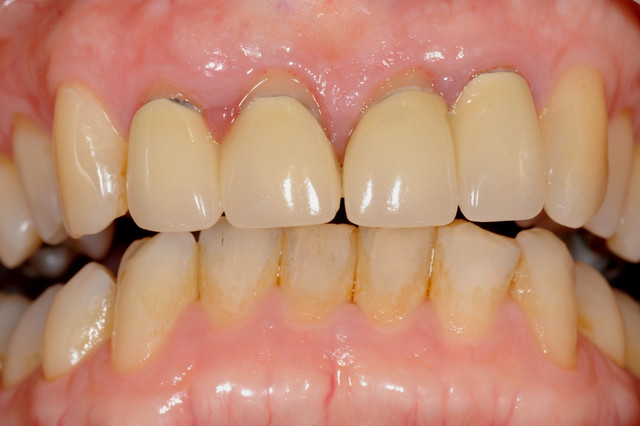

E.max crown try in 280713

#Togias 190713 nora